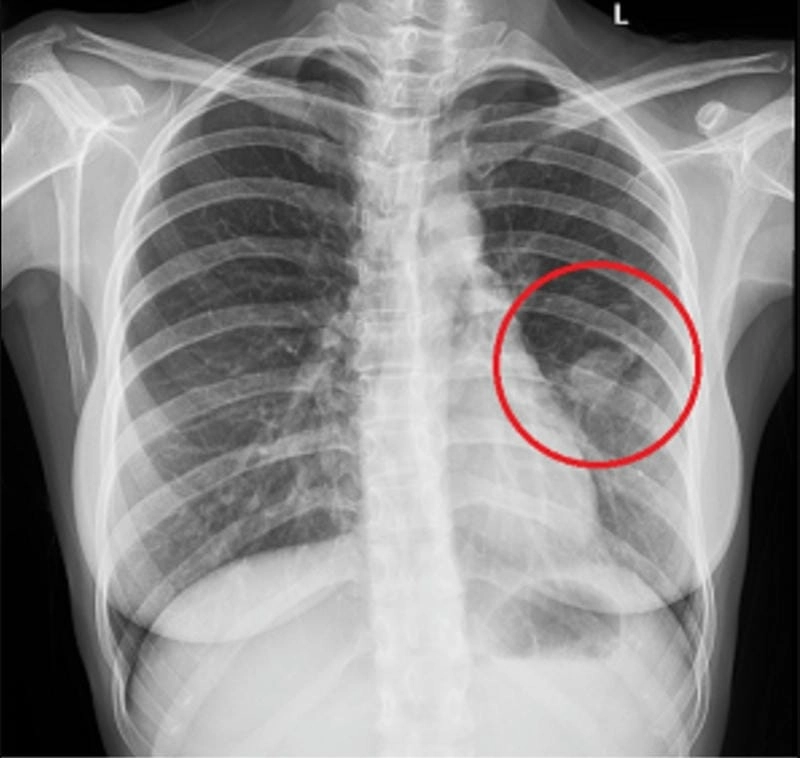

Hình ảnh bệnh lao phổi là tài liệu tham khảo quan trọng giúp người bệnh và bác sĩ dễ dàng nhận biết dấu hiệu bất thường. Việc quan sát hình ảnh X-quang, CT phổi giúp chẩn đoán chính xác mức độ tổn thương và đưa ra phương án điều trị kịp thời.

Bạn sẽ phải rùng mình khi chiêm ngưỡng hình ảnh bệnh lao phổi là như thế nào dưới ống kính y học thực tế. Những bức ảnh chụp X-quang cho thấy phổi bị tổn thương nặng, xuất hiện những đốm trắng mờ như bóng ma ám ảnh. Không chỉ là các tổn thương vật lý, đây còn là những “chứng tích sống” của căn bệnh âm thầm hủy hoại cơ thể qua từng hơi thở. Từ viêm nhẹ đến tổn thương lan rộng, hình ảnh bệnh lao phổi khiến người xem không thể rời mắt vì mức độ nghiêm trọng mà nó thể hiện rõ ràng qua từng chi tiết.

Chuẩn đoán chính xác nhờ hình ảnh x quang lao phổi